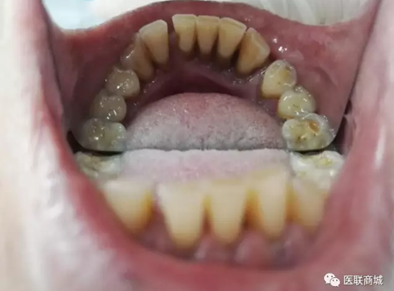

該患者本身就有慢性牙周炎,加上高血壓的基礎(chǔ)疾病,長期服用硝苯地平,這個是導(dǎo)致藥物性牙齦增生常見藥物之一,針對這樣的患者在牙周基礎(chǔ)治療時必要的,但在基礎(chǔ)治療的同時,一定要建議患者更改降壓藥物,同時必要時手術(shù)切除增生牙齦,可以達(dá)到很好的效果,見圖片(圖中白色為雙氧水沖洗后效果)。